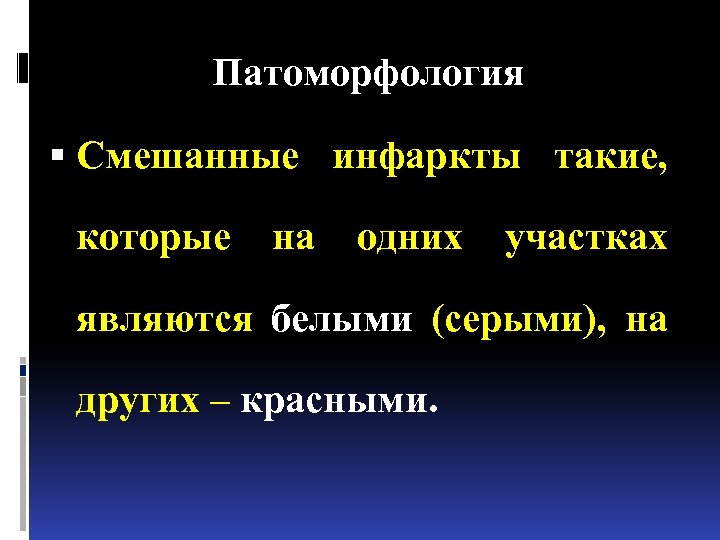

Патоморфология Смешанные инфаркты такие, которые на одних участках являются белыми (серыми), на других – красными.

Патоморфология Смешанные инфаркты такие, которые на одних участках являются белыми (серыми), на других – красными.